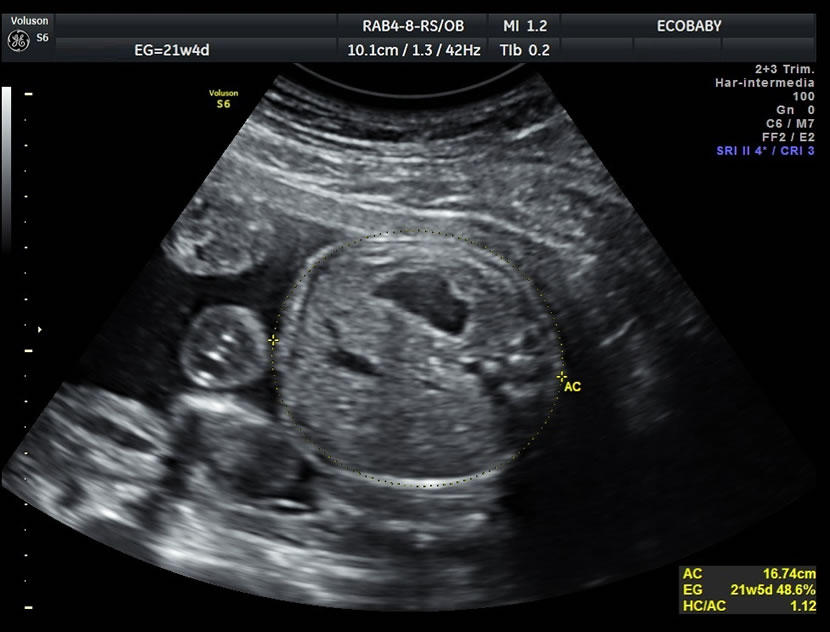

Cerebro, cuello, cara, tórax, corazón (diferentes cortes que muestran las cavidades y la correcta entrada y salida de arterias y venas), abdomen (normalidad de la pared, estómago, intestino, riñones, vejiga), miembros inferiores y superiores y columna vertebral.